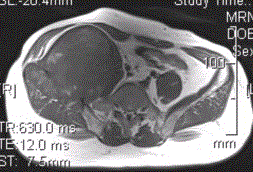

患者男,28岁,右下腹及臀部疼痛5个月余。查体:右髂骨外后侧压痛,右下腹可触及一软组织包块,质韧,固定。行骨盆正位CR、骨盆CT及MR扫描见下图。...

问题 患者男,28岁,右下腹及臀部疼痛5个月余。查体:右髂骨外后侧压痛,右下腹可触及一软组织包块,质韧,固定。行骨盆正位CR、骨盆CT及MR扫描见下图。 此病变最可能的诊断是

选项 A.骨囊肿 B.动脉瘤样骨囊肿 C.骨结核 D.骨巨细胞瘤 E.硬韧带样纤维瘤

答案 B